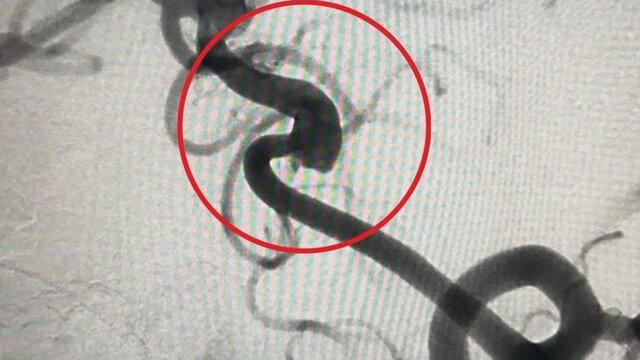

По информации ведомства, врачи диагностировали 9-летнему мальчику аномальное расширение стенки ствола основной артерии, отвечающей за кровоснабжение органа центральной нервной системы. Выявленная патология могла стать причиной инсульта или кровоизлияния в мозг.

В ходе операции медики провели катетер к сосудам мозга через бедренную артерию и имплантировали поток-перенаправляющий стент, разместив его в области аневризмы. Благодаря успешному вмешательству хирургам удалось предотвратить риск инсульта у пациента.